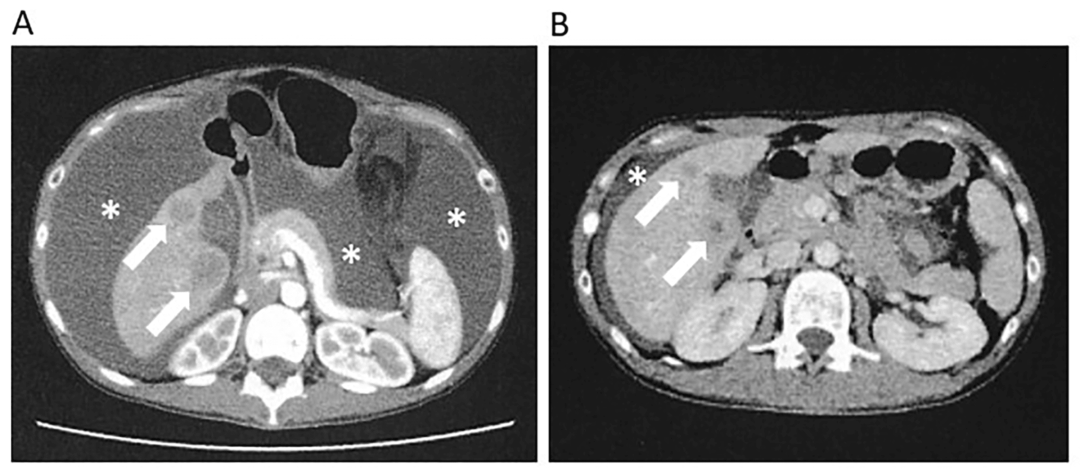

原发肿瘤缩小,多发转移消失:治疗进行到第 142 天时,PET-CT 检查显示,患者体内的肺转移和腹膜播散情况已经消失,肝转移和原发性病变也明显缩小。